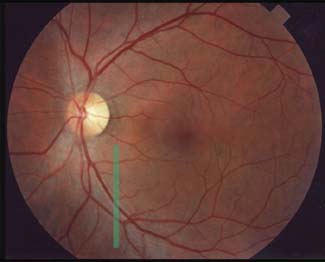

Lokalizovaný výpadek nervových vláken byl popsán poprvé teprve roku 1973 Hoytem. Je vějířovitého tvaru, připomínající ocas komety. Vyskytuje se u 20% glaukomů, není však pro glaukom specifický (drůzy, chorioretinální jizvy, dlouho trvající edém disku, pozánětlivá atrofie). Není u zdravých očí.

U glaukomu bývá v časných a středních stádiích, častěji u fokláního ischemického typu, v místech, kde byly před více než 2 měsíci peripapilární hemorhagie, kde exkavace je protažena k okraji terče a kde je rozsáhlejší peripapilární atrofie. Nebývá u pokročilého glaukomu. Airaksinen: výpadky předcházejí perimetrickým změnám.

Peripapilární hemorhagie u glaukomu

Plaménkovité nebo třískovité hemorhagie na okraji terče jsou vyskytují u 4-7% pacientů s glaukomem, hlavně u počínajícího a středně pokročilého poškození zrakového nervu. U pokročilého glaukomu s totální ztrátou lemu se již nevyskytují. Nejčastěji jsou v horním a dolním temporálním kvadrantu terče. Ve dvou epidemiologických studiích byla nalezena frekvence hemorhagií na očích bez glaukomu jen v 1%. Tato vysoká specificita 99% je nám nápomocná k včasné diagnóze glaukomu a svědčí na jeho progresi. Peripapilární hemorhagie však nejsou specifické jen pro glaukom (přední ischemická neuropathie, trombosa centrální vény sítnice, hypertonitcká neuroretinopathie, diabetická retinopathie).

Patogeneze

Předpoklad, že posunem kribriformní laminy dozadu dojde k ruptuře povrchových krevních cév neobstojí před klinickou zkušeností, že při výrazném zvýšení tenze po kontusi oka tyto hemorhagie nevznikají. Také názor, že jde o ischemický proces, neodpovídá tomu, že u glaukomu nenacházíme vatovitá ložiska, typická pro infarkty ve vrstvě nervových vláken. Nevíme ani, zda krvácení pochází s arteriol, venul nebo z kapilár peripapilární radiální pleteně.

Průběh

Sonnsjo a spol. fotografovali po 14 denních intervalech po dobu 2

let terče s hemorhagiemi u dvou pacientů s glaukomem. Hemorhagie se

objevovaly znovu a znovu na stejném místě, což by mohlo způsobit

mylnou představu, že se hemorhagie jen pomalu resorbují. Krev

pronikala do periferie podél nervových vláken a po resorpci na disku

krev někdy ještě přetrvávala peripapilárně a působila dojmem

hemorhagie nesouvisející s terčem.

Hemorhagie můžeme nalézt u všech typů glaukomu, nejčastější jsou u

fokálního ischemického typu, méně časté u glaukomu s vyšší tenzí. Je

možné, že vyšší nitrooční tenze zastaví krvácení rychleji, takže

hemorhagie jsou u glaukomu s vyšší tenzí menší a rychleji se

vstřebávají. Naopak u glaukomu nízké tenze bývají větší a

vstřebávají se pomalu. Možná právě to je důvodem, proč hemorhagie

častěji vidíme u glaukomu s nízkou tenzí.

Asi po 2 měsících od vzniku hemorhagií dochází k výpadku svazečku

nerovvých vláken.